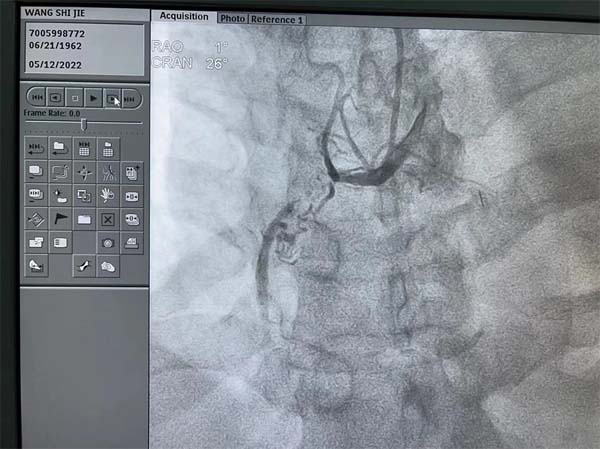

应急总医院心血管内科的疾病经常是突如其来,来势汹涌。一位59岁的男性患者在常规冠脉CT检查中发现右冠状动脉(RCA)有严重的狭窄,同时合并有十二指肠球部溃疡,患者平时没有严重的胸闷胸痛等症状,入院心电图和超声心动图检查也都正常,患者本人对检查结果还有一些意外。吴迪副院长查看该病人冠脉CT后给予了准确判断,患者RCA是完全闭塞(CTO)病变,术前一天根据患者情况制定了术中抗凝抗栓方案,患者进入导管室后实施冠脉造影,果然不出所料:RCA在近端完全闭塞,左冠脉向RCA提供部分侧支循环,RCA闭塞处有部分前向桥侧支,闭塞段超过2cm。闭塞段有部分钙化,远端血管可供登录部分比较细,增加了开通困难。吴迪副院长仔细研判造影图像,并结合冠脉CT图像,评估患者RCA闭塞血管的走形,并充分与患者本人及家属沟通,详细告知病情。

CTO病变目前还是冠脉介入治疗的难点,即便最有经验的冠脉介入医生,成功开通CTO病变的成功率也只有80-90%。吴迪副院长审时度势,迎难而上,制定前向开通方案,选择了强支撑的指引导管,在Sion导丝和微导管送至RCA闭塞处近段,逐步升级导丝,精确操控导丝,终于在微导管支撑下,多次突破闭塞处坚硬病变后,Gaia2导丝顺利到达RCA远段真腔,把微导管送至RCA远段后交换成工作导丝,从小球囊到大球囊,逐渐将闭塞病变充分预处理后置入两枚支架,RCA成功再次恢复通畅,血流恢复正常TIMI3级。手术在最短时间结束,患者平稳转至CCU监护病房,患者和家属一直悬着的心终于放了下来。患者激动地说:“心内科团队把80-90%可能变成了100%成功,太棒了!”